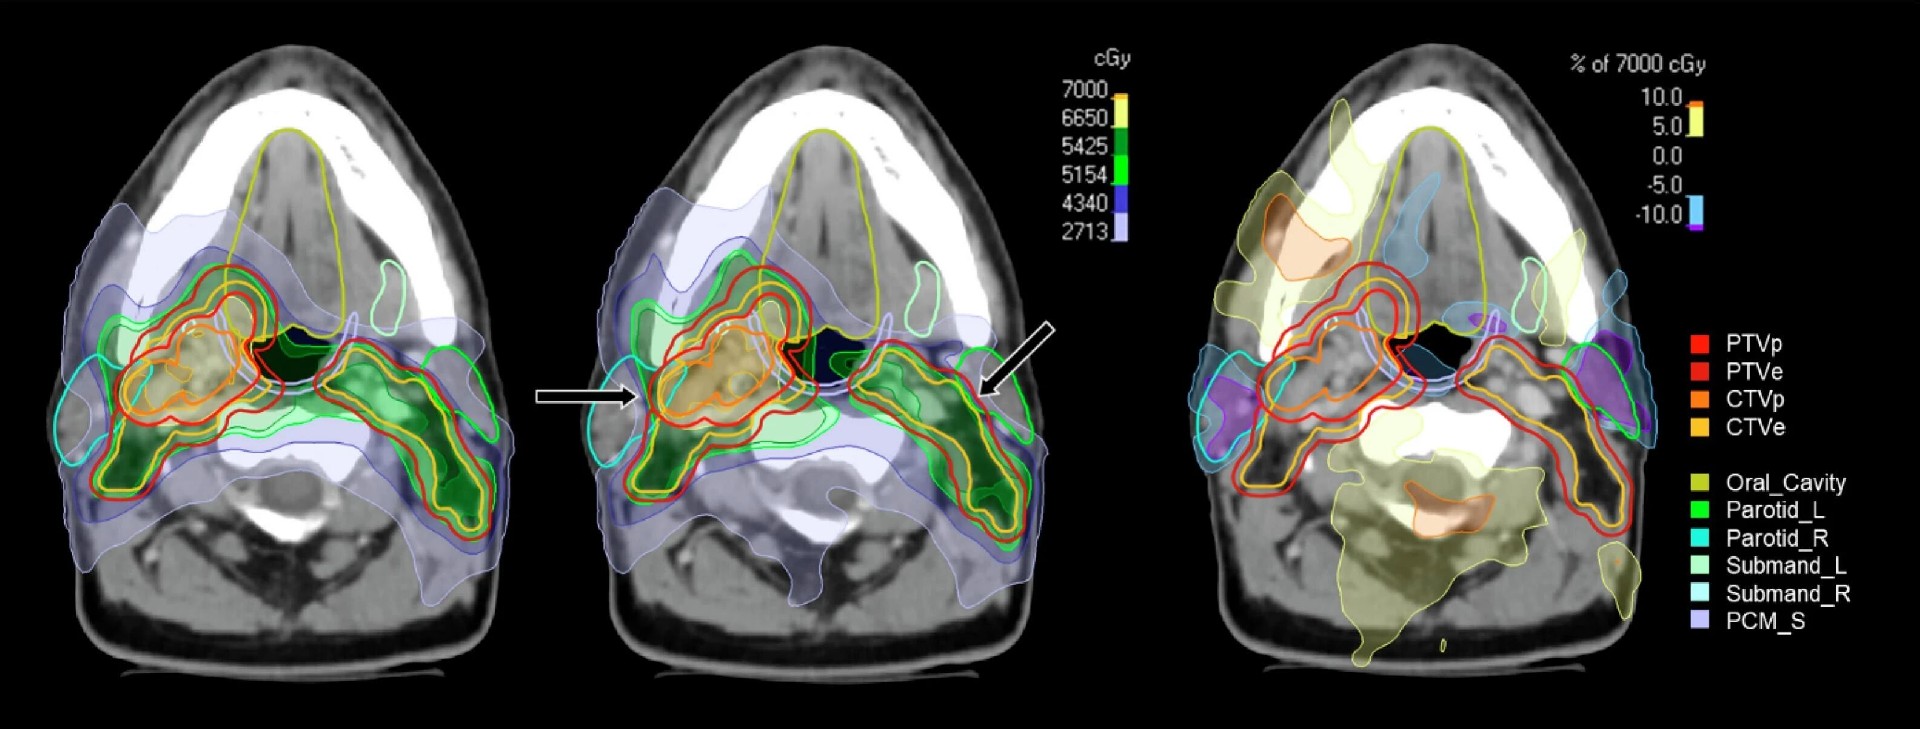

图3 典型患者常规与稳健计划的剂量分布对比

轴位剂量分布与剂量差图直观显示,稳健计划通过上调危及器官优化权重、设置 CTV 稳健目标,在完全保障 CTV 覆盖的前提下,腮腺等关键危及器官区域实现 5%~10% 的相对剂量降低,剂量分布更贴合个体化解剖结构,正常组织保护效果显著提升。